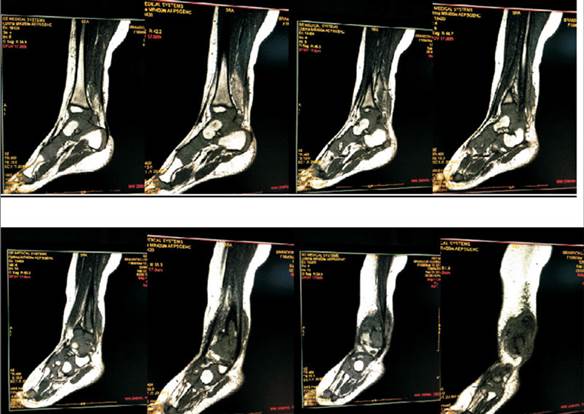

A las 72 horas del ingreso se realiza resonancia nuclear magnética (RNM) de tobillo derecho: en T1 en tercio inferior del peroné e interlínea articular tibiotarsiana imágenes hipointensas, lesión en astrágalo con imagen en sacabocado. En T2 imágenes hiperintensas (Figura 2, Figura 3 y Figura 4).